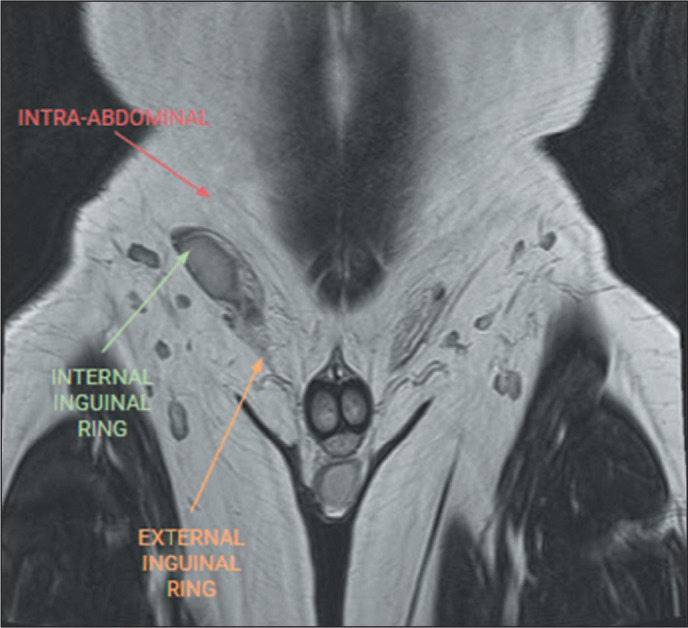

Magnetic resonance imaging is an essential tool for the assessment of the scrotum, particularly in cases with inconclusive ultrasound findings. It has a great capacity to differentiate between intratesticular and extratesticular lesions, as well as between neoplastic and non-neoplastic lesions. By providing an accurate characterization of lesions, magnetic resonance imaging plays a crucial role in preoperative tumor staging and decision-making. This pictorial essay highlights the key non-neoplastic and neoplastic testicular pathologies, as evaluated by magnetic resonance imaging. The recognition of these pathologies underscores the role the radiologists play in the care of patients with scrotal lesions, by providing an appropriate evaluation of the relevant imaging characteristics.